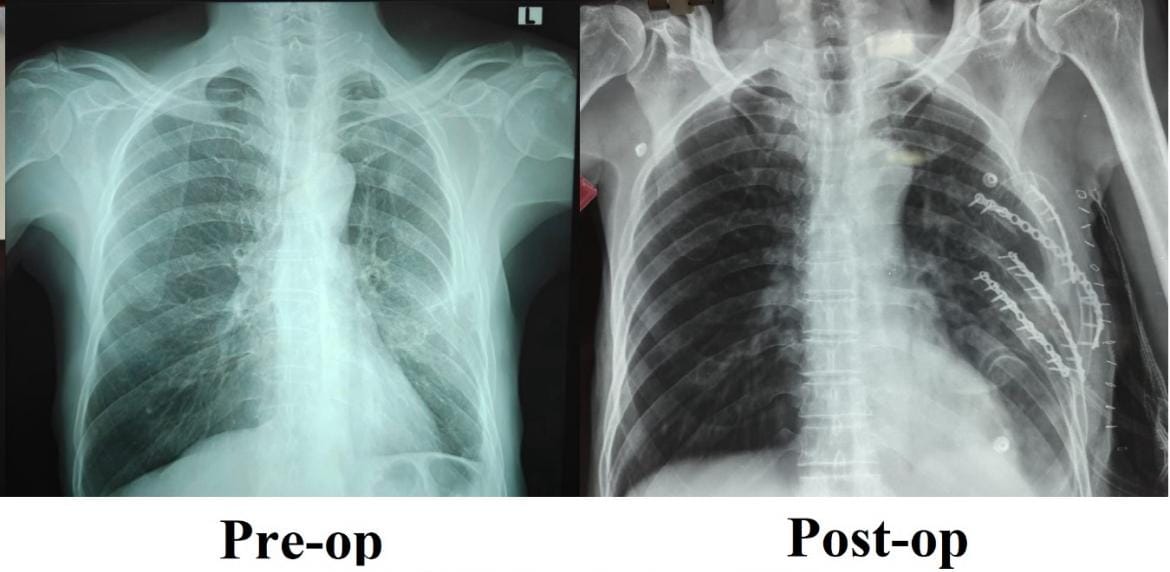

The Trauma Surgery team at SRM Medical College Hospital & Research Centre has successfully performed its first rib stabilisation surgery, marking a significant milestone in advanced trauma care at the institution.

The patient, who had sustained multiple rib fractures in a road traffic accident, continued to suffer from severe chest pain for over a month despite optimal pain management and structured physiotherapy. The condition led to difficulty in deep breathing, disturbed sleep, and restricted daily activity due to poor healing and instability of the fractured ribs.

Recognising the need for surgical intervention, the trauma team led by Dr. Vijayan P, Associate Professor, Department of General Surgery, undertook a specialised rib fixation procedure to realign and stabilise the fractured ribs, enabling proper anatomical healing.

Following surgery, the patient showed rapid and marked improvement. Breathing became comfortable, mobility improved significantly with minimal pain, and the patient was able to resume routine activities with renewed confidence.

“This surgery was crucial because prolonged rib instability can severely affect breathing, mobility, and overall recovery. By stabilising the ribs surgically, we were able to relieve pain, improve lung function, and help the patient regain normal daily activity much faster. This outcome reinforces the importance of advanced trauma interventions when conservative treatment is no longer sufficient.”

This intervention is the first rib stabilisation surgery performed at SRM Medical College Hospital and is among the very few such procedures carried out in the city, reflecting the institution’s expanding capabilities in complex trauma management.